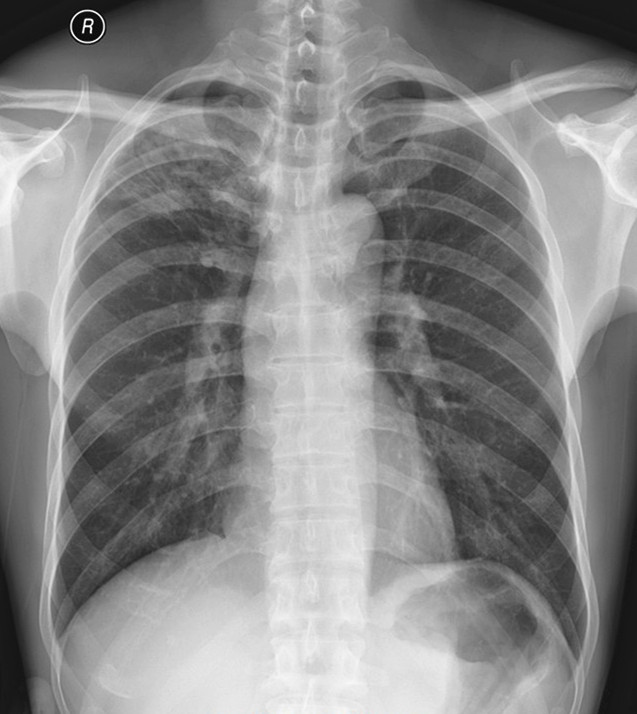

图(二)、抗结核治疗一个多月后复查正位胸片: